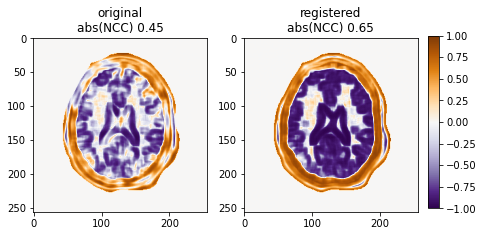

登録前後のLocal NCC2を計算すると,各ピクセルにおいてNCCの絶対値が向上していることが確認できます.